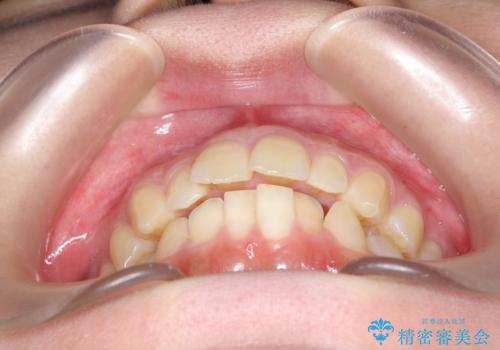

- 前歯が少し前に出ているのが気になるとのことで来院されました。

インビザラインにて上顎の歯を全体的に後方に移動させて前歯を引っ込める計画としました。